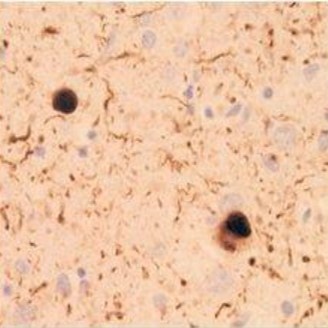

免疫組織染色

| 動物種 | ヒト (レビー小体型認知症患者) |

| 部位 | 脳 |

<データ提供>

東京大学大学院 医学系研究科 岩坪先生